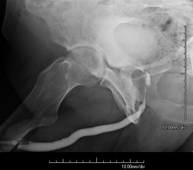

- Hipsterosalpingografia (HSG)

Prova diagnòstica que consisteix en la visualització i l'estudi de l'úter i les trompes de Falopi mitjançant l'ús de raigs X i un mitjà de contrast. La pacient haurà de realitzar un tractament antibiòtic profilàctic i es recomana la presa d'un sedant suau una hora abans de la prova. - Trans-Kher Cholangiography